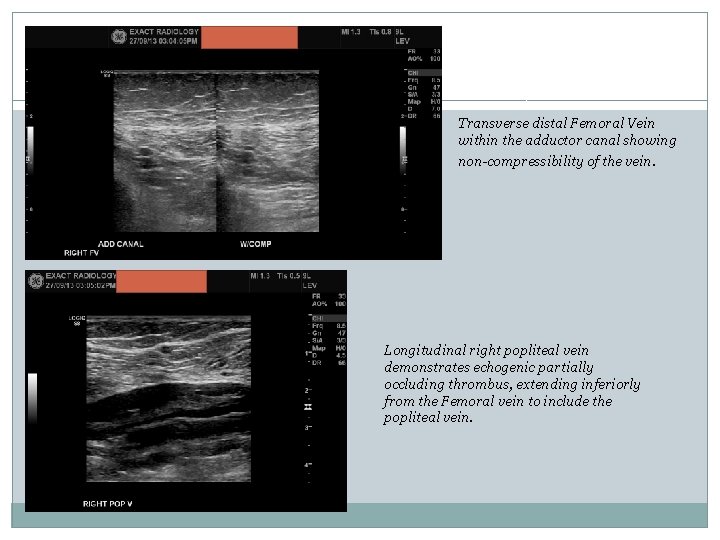

Transverse distal Femoral Vein within the adductor canal showing non-compressibility of the vein. Longitudinal right popliteal vein demonstrates echogenic partially occluding thrombus, extending inferiorly from the Femoral vein to include the popliteal vein.

Transverse Popliteal vein showing echogenic thrombus and non-compressibility, again confirming a DVT, however it is most likely chronic.